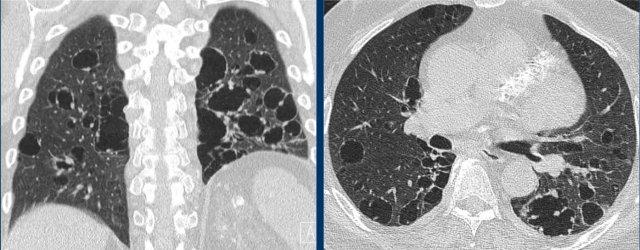

LAM biểu hiện với số lượng lớn các nang hình tròn, bờ đều đặn, phân bố rải rác khắp nhu mô phổi.

- Nhiều nang ở một phụ nữ trẻ. Lưu ý hình dạng tròn đều và phân bố lan tỏa.

- Trường hợp LAM nặng. Khi có tiền sử hút thuốc lá, chẩn đoán phân biệt cần đặt ra là LCH (giai đoạn tiến triển).

- Tràn dịch màng phổi (dịch dưỡng chấp) ở bệnh nhân LAM.

- Phân bố lan tỏa trong LAM.

Các hình ảnh này thuộc về một phụ nữ 39 tuổi với triệu chứng khó thở.

Chẩn đoán có khả năng nhất là gì?

Nhận xét hình ảnh

Có nhiều nang thành mỏng.

Lưu ý các nang phân bố đều khắp hai phổi.

Các ngách màng phổi cũng bị tổn thương (mũi tên).

Điều này cho phép loại trừ chẩn đoán LCH.

Chẩn đoán có khả năng nhất là LAM.

Đây là một ví dụ khác của LAM.

Có nhiều nang thành mỏng phân bố đều khắp hai phổi, điển hình cho LAM, nhưng trong trường hợp này kết hợp với tràn dịch màng phổi bên phải (mũi tên).

Các tế bào LAM có thể gây tắc nghẽn hệ thống bạch huyết trong lồng ngực và tạo ra tràn dịch màng phổi dưỡng chấp.

LAM là bệnh phổi dạng nang duy nhất có thể thấy sự kết hợp giữa các nang và tràn dịch màng phổi.

Ngoài ra, nhiều u cơ mỡ mạch máu (angiomyolipoma) được phát hiện ở vùng bụng trên.

Bệnh nhân này được xác định mắc LAM liên quan đến phức hợp xơ cứng củ (TSC – tuberous sclerosis complex).

Tỷ lệ hiện mắc u cơ mỡ mạch máu trong LAM tản phát là 40-50% và trong LAM liên quan TSC vào khoảng 80%.

Đây là trường hợp LAM nặng với nhu mô phổi bị tổn thương lan tỏa.

Nhìn chung, LAM là bệnh lý tiến triển với tiên lượng xấu.